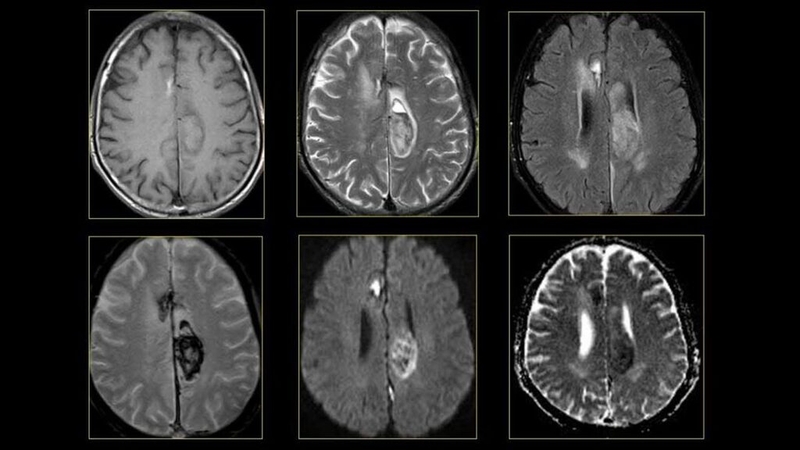

Trên hình ảnh T1W, khối u màng não sẽ có tín hiệu giống với các nhu mô não xung quanh, đồng thời chuỗi xung này chủ yếu dùng để đánh giá xuất huyết trong u hoặc u hoại tử.

Tuy nhiên, các khối u trên hình ảnh T1W FAT SAT sau khi tiêm Gadolinium (thuốc cản quang) ngấm thuốc rất mạnh và rõ nét, từ đó giúp xác định chính xác vị trí, kích thước cũng như mức độ xâm lấn xung quanh của khối. Trong khi đó, khối u màng não khó có thể tiên lượng được trên các chuỗi xung không tiêm thuốc cản quang.

Hầu hết các khối u màng não đều cần phải chụp MRI có tiêm thuốc cản quang nhằm chẩn đoán xác định, đồng thời giúp phân biệt với các loại khối u khác. Điều này giúp bác sĩ tiên lượng bệnh một cách chính xác để đưa ra được phương pháp điều trị phù hợp nhất cho bệnh nhân.

Trên hình ảnh T2W, các khối u màng não thường sẽ tăng tín hiệu một cách rõ nét. Điều này giúp bác sĩ có thể nhìn thấy rõ ràng hơn về đường bờ, ranh giới và kích thước của khối u màng não.

Bên cạnh đó, hình ảnh T2W cũng giúp bác sĩ biết được tính chất và bản chất bên trong của khối u, đồng thời giúp đánh giá mức độ chảy máu xung quanh khối u và đè đẩy nhu mô não.

Hơn nữa, trên chuỗi xung đảo ngược T2 Flair sẽ giúp đánh giá rất tốt về sự phù nề. Đây là một chuỗi xung cực kỳ quan trọng trong kỹ thuật chụp cộng hưởng từ sọ não và luôn được chụp trước tiên nhằm đánh giá tổng thể nhu mô não.